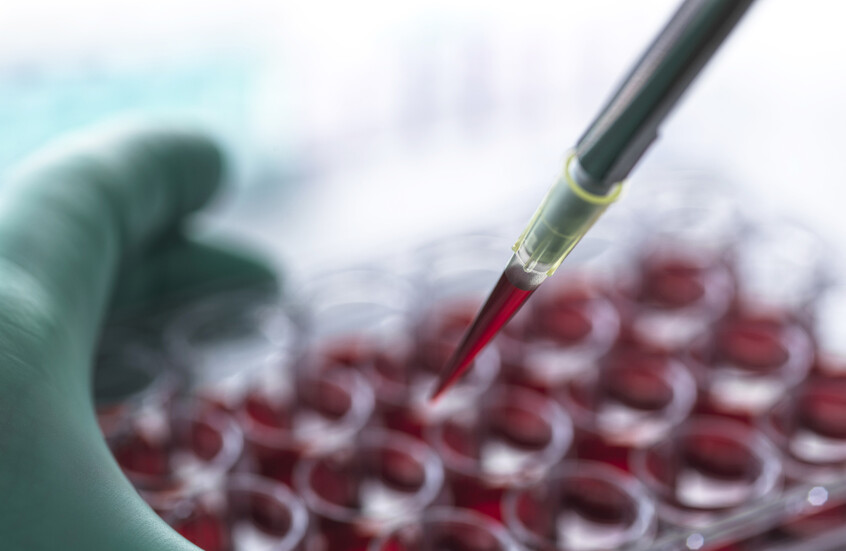

لماذا يصاب البعض بآثار جانبية بعد لقاحات "كوفيد-19"؟

الآثار الجانبية المؤقتة، بما في ذلك الصداع، والتعب والحمى هي علامات تدل على أن جهاز المناعة ينتعش، ما يعتبر استجابة طبيعية للقاحات.

دراسة تكشف أثر التطعيم ضد "كوفيد-19" لدى مرضى غسيل الكلى مقارنة بمن يخضعون لعمليات الزرع!

ويشرح الدكتور بيتر ماركس، مدير اللقاحات في إدارة الغذاء والدواء الأمريكية، لماذا يشعر البعض بآثار جانبية بعد لقاحات "كوفيد-19"، قائلا يوجد للجهاز المناعي ذراعان رئيسيان، ويتدخل الأول، بمجرد أن يكتشف الجسم وجود دخيل أجنبي، وهو الجرعة الأولى من اللقاح. وتتدفق خلايا الدم البيضاء إلى موقع اللقاح، ما يؤدي إلى حدوث التهاب مسؤول عن القشعريرة والوجع والتعب والآثار الجانبية الأخرى.

وتميل خطوة الاستجابة السريعة لجهاز المناعة لديك إلى التضاؤل مع تقدم العمر، وهو أحد الأسباب التي تجعل الأشخاص الأصغر سنا يبلغون عن الآثار الجانبية أكثر من كبار السن. كما أن بعض اللقاحات تثير ردود فعل أكثر من غيرها.

ومع ذلك، يتفاعل الجميع بشكل مختلف. إذا لم تشعر بأي شيء بعد يوم أو يومين بعد أي من الجرعتين، فهذا لا يعني أن اللقاح لا يعمل.

أما الذراع الثاني، فإنه يحفز جهاز المناعة لديك، والذي سيوفر حماية حقيقية من الفيروس عن طريق إنتاج الأجسام المضادة.

وبالنظر إلى أن لقاحات "كوفيد-19" تتفاعل بشكل مختلف مع أجسادنا فإنه عندما ينشط الجهاز المناعي، يسبب أحيانا تورما مؤقتا في الغدد الليمفاوية، مثل تلك الموجودة تحت الذراع.

دواء شائع للسكري يظهر نتائج واعدة كعلاج للالتهاب الرئوي الناتج عن "كوفيد-19"

ويتم تشجيع النساء على جدولة تصوير الثدي بالأشعة السينية الروتينية قبل التطعيم لتجنب العقدة المتورمة التي يتم الخلط بينها وبين السرطان.

وليست كل الآثار الجانبية روتينية. ولكن بعد مئات الملايين من جرعات اللقاح التي تم إعطاؤها حول العالم، ومراقبة السلامة المكثفة، تم تحديد القليل من المخاطر الجسيمة. وأبلغت نسبة ضئيلة من الأشخاص الذين حصلوا على لقاحات من إنتاج أسترازنكا وجونسون أند جونسون عن نوع غير عادي من الجلطات الدموية. واحتفظت بعض البلدان بهذه اللقاحات لكبار السن، لكن السلطات التنظيمية تقول إن فوائد تقديمها ما زالت تفوق المخاطر.

ويعاني الناس أحيانا أيضا من ردود فعل تحسسية خطيرة. ولهذا السبب يُطلب منك البقاء لمدة 15 دقيقة تقريبا بعد الحصول على أي نوع من لقاح "كوفيد-19"، لضمان إمكانية علاج أي رد فعل بشكل سريع.

وأخيرا، تحاول السلطات تحديد ما إذا كان التهاب القلب المؤقت الذي يمكن أن يحدث مع العديد من أنواع العدوى قد يكون أيضا أثرا جانبيا نادرا بعد لقاح mRNA، وهو النوع الذي تصنعه شركات فايزر ومودرنا. ولا يستطيع مسؤولو الصحة في الولايات المتحدة معرفة ما إذا كان هناك رابط حتى الآن، لكنهم يقولون إنهم يراقبون عددا صغيرا من التقارير، معظمها من المراهقين الذكور أو الشباب.

المصدر: ميديكال إكسبريس